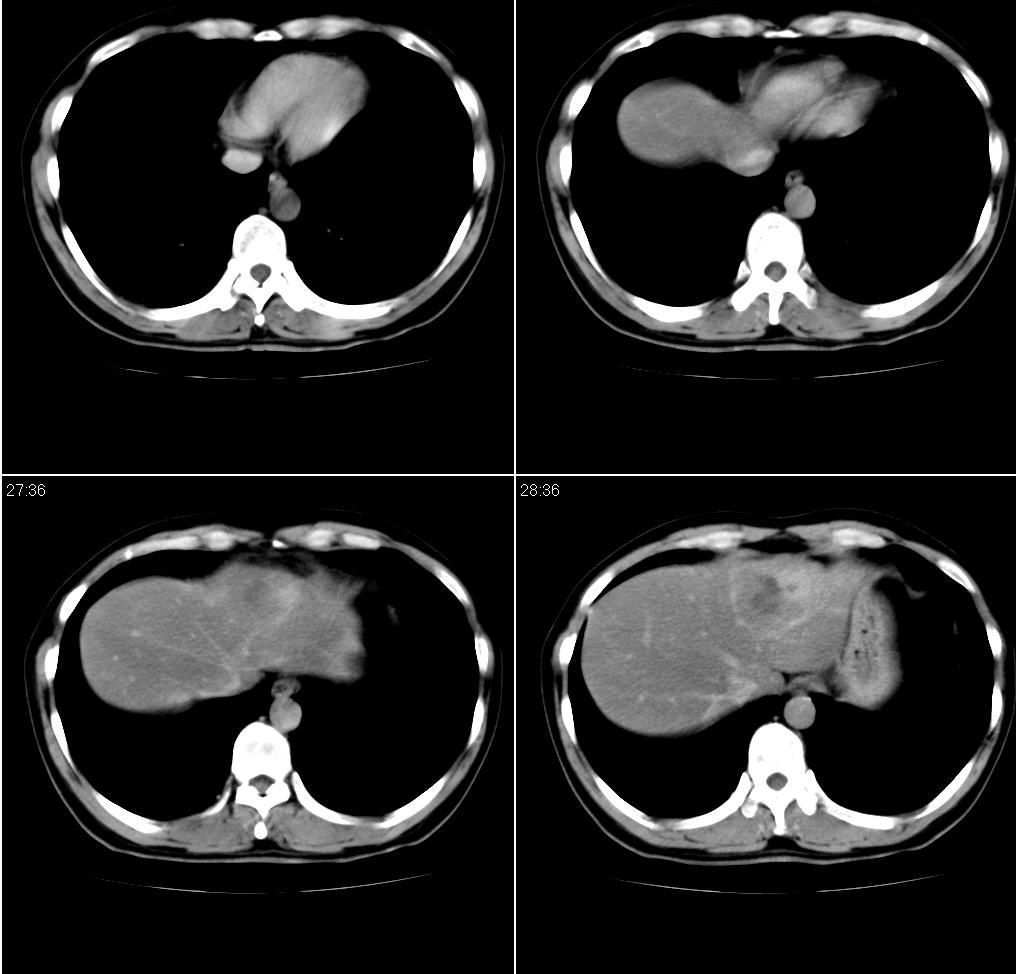

男,43岁。体检发现肝脏病变

肝局灶性脂肪肝 肝左叶外侧段占位病变,建议加强

考虑肝左叶癌并脂肪肝,肿块在脂肪肝衬托下呈高密度影,其内可见坏死灶,建议增强

肝右叶密度均匀减低,左叶增大,表面凹凸不平,内有低密度影。脾不大其密度较肝稍高。考虑1脂肪肝2肝左叶占位。建议增强。

1)局灶性脂肪肝2)肝左叶外侧段内占位,建议强化

肝局灶性脂肪肝 肝左叶外侧段1)肝海绵状血管瘤2)肝ca

肝局灶性脂肪肝 肝左叶外侧段占位病变(肝癌?),建议增强。

肝右叶密度均匀减低,左叶增大,表面凹凸不平,内有低密度影。考虑1局灶性脂肪肝 2肝左叶占位。建议增强。

下缘与胃窦关系密切,会不会是来源于胃的间质瘤??

增强后诊断很明确了,缓慢结节样强化:肝内多发血管瘤